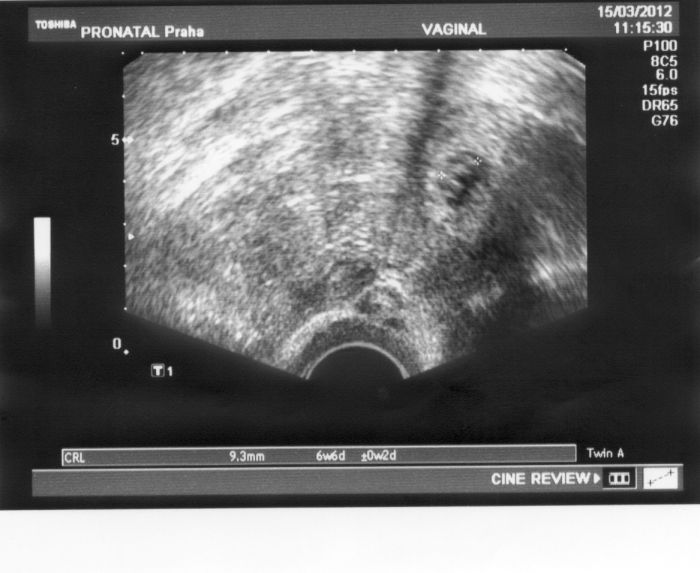

Já se musím pochlubit. Byla jsem dneska na UZ a všechno je úúúúplně super. Už jsem dostala i fotečku, ale je na ní jenom takový malý flíček

Jsme s partnerem úplně mimo. Pátý pokus IVF. Teprve 7+2, ale naše mimi je bojovník.